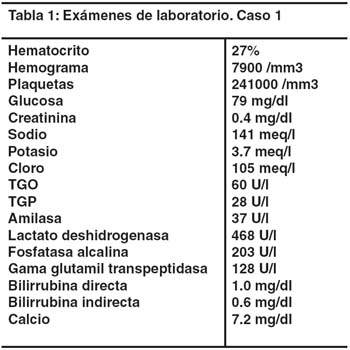

La paciente lucía moderadamente pálida y deshidratada, sin ictericia, adenopatías ni edema. El útero, con altura de 34cm, era adecuado a la edad gestacional. Presentaba dolor intenso a la palpación en el epigastrio, sin rebote. Los ruidos hidroaéreos estaban presentes y no se encontró hepatomegalia ni esplenomegalia. La actividad y los latidos cardíacos fetales eran normales. Los exámenes de ayuda diagnóstica se muestran en la tabla 1.

La ecografía mostró una masa quística de 7cm de diámetro en la región subhepática. La tomografía mostró una imagen quística hipodensa, redondeada, de 7x7cm, homogénea, y de pared delgada, que se extendía desde el hilio hepático hasta la cabeza del páncreas (figura 1).

En el cuarto día de hospitalización se dio término a la gestación por cesárea, con un recién nacido vivo normal. En los días siguientes el dolor disminuyó notablemente. Posteriormente se realizó una colangiografía retrógrada endoscópica (CPRE) en la que el contraste inyectado en la vía biliar no fue visible en la fluoroscopía. Inmediatamente después una nueva tomografía mostró material de contraste dentro de la imagen quística subhepática (figura 2). Se confirmó así el diagnóstico de quiste de colédoco.